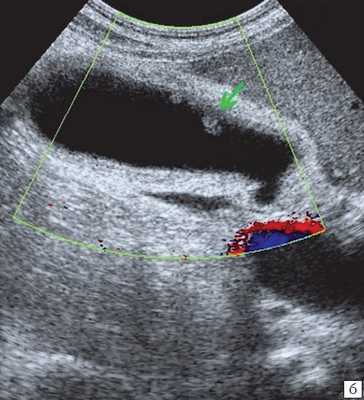

Специальную сверхтонкую струну-проводник удалось провести в сегментарный проток правой доли печени (рис. 2), после чего принято решение первоочередно расширить просвет протока специальными эндоскопическими бужами (рис. 3, 4), постепенно увеличивая диаметр последних.

Когда необходимый диаметр был достигнут, выполнено стентирование левого долевого желчного протока печени (рис. 5).

Через установленный ранее чрескожный дренаж проведено антеградное бужирование, а затем эндоскопическая установка второго стента в правый долевой проток печени (рис. 6-7).